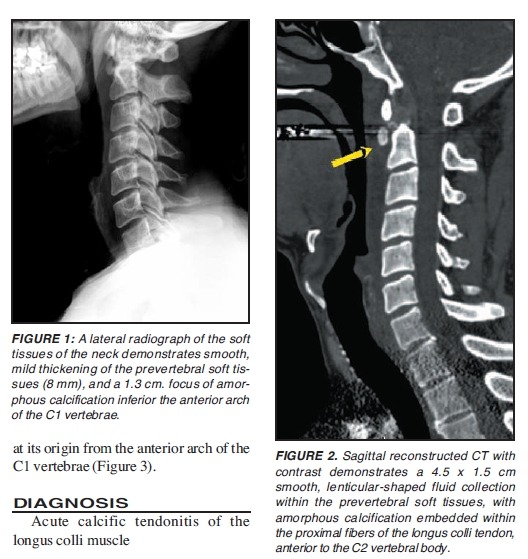

드물지만 neck pain 통찰하는데 중요한 질환 longus colli tendinitis

흉쇄유돌근과 함께 tendinitis가 발생한다. 심지어 calcific tendinitis까지.

첨부파일 Acute calcific tendinitis of the longus colli muscle.pdf

첨부파일 Acute calcific prevertebral tendonitis of longus colli.pdf